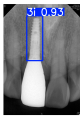

| Image Resolution = 825 × 1200 | ||||

| Test Image 1–4 | ![]() | ![]() | ![]() | ![]() |

| Accuracy | 94.13% | 95.29% | 92.88% | 91.80% |

| Recall | 96.71% | 94.03% | 93.88% | 92.15% |

| Model reference time | 6.57 ms | 7.08 ms | 7.12 ms | 6.43 ms |

| Dentists’ average diagnostic time | 2.78 s | 4.55 s | 7.78 s | 7.23 s |